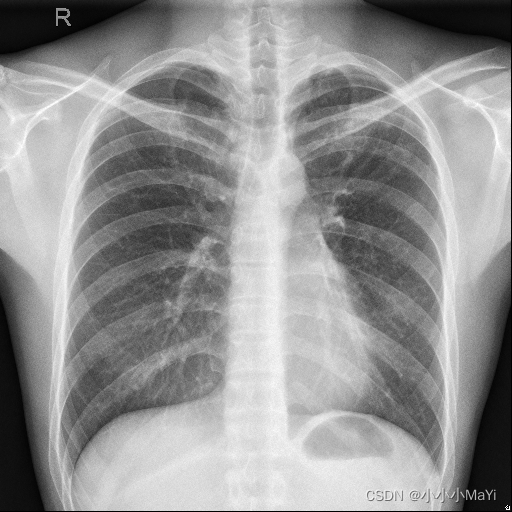

目的:训练Swin-Unet分割肺部区域

输入原图

此文中只用了整个数据集中的345张图像用来完成整个分割任务!

这是本文用到的345张图像和对应的mask